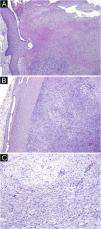

Microscopic examination showed a well-defined tumoral lesion covered by a sclero-hyaline capsule, with ulceration and necrosis of the overlying epidermis and dermis (Fig. 2A and B). The lesion consisted of two patterns: more compacted areas composed of ovoid to spindle-shaped cells with eosinophilic cytoplasm and indistinct cell boundaries (Antoni A pattern) with occasional nuclear palisading (Verocay bodies), and others areas more loosed and hypocellular consisting of cells with clear cytoplasm and well-defined boundaries, with collagenous stroma with myxoid areas and hyalinized wall vessels (Fig. 2C).

(A) Ulceration and necrosis with suppuration of the adjacent epidermis and dermis (Hematoxylin & eosin, ×40). (B) The lesion was well-delimited by a sclero-hyaline capsule (Hematoxylin & eosin, ×40). (C) Tumoral lesion consisting of ovoid to spindle-shaped cells, with areas of eosinophilic cytoplasm and indistinct boundaries (Antoni A pattern) alternating with more loose and hypocellular areas of cells with clear cytoplasm and well-defined boundaries (Antoni B pattern) (Hematoxylin & eosin, ×100).